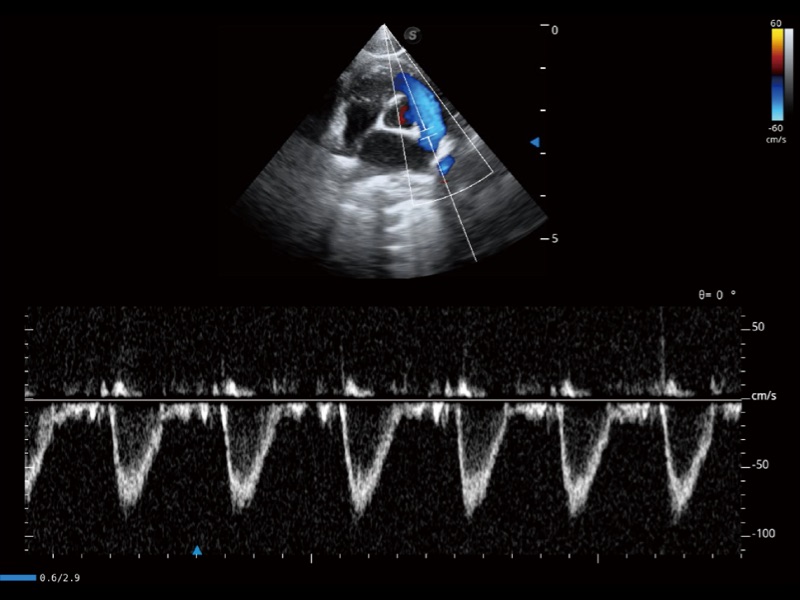

能够基于左心室壁追踪和辛普森法,自动计算射血分数,支持多个可移动点描迹,与手动测量相比,极大节省了动物医生的时间和精力。

通过创新的 Matrix E自适应滤波器和超长时间域算法,极大提升超低速微细血流的检出能力,同时更精准地滤除软组织和噪声信号,为兽用医生提供以往无法通过常规血流获得的疾病诊断信息。

通过色彩血流和实时宽景相结合,可观察到完整的静脉或动脉的血流,方便医生检查。实时扫查过程中,如有任何操作失误也可以很容易地进行回扫擦除,而不会中断扫查。

通过360度任意调节3条M型取样线,在同一心动周期上观察心脏不同位置的运动曲线,得到准确的心功能测量数据,有效评估心肌运动及左心室功能。

实时用颜色表示心肌组织运动,观察和定量组织的运动情况,对快速检测与评估心肌的灌注和活性、电传导及心肌收缩和舒张功能等均能提供重要的诊断信息。